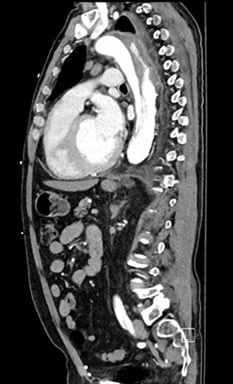

The gold standard for diagnosis is the computed tomography angiography (CTA) because of its speed, high sensitivity, and high specificity for aortic pathology. The sensitivity and specificity of CTA for acute aortic dissection approaches 100%.1,4,28-30 (See Figures 2-4.) An important point when ordering the CTA is to specifically state the reason, such as “possible aortic dissection,” so the correct CT imaging protocol will be done to maximize accuracy.

Figure 2. CTA Showing Dissection of the Descending Thoracic Aorta with Sagittal View |

![]() |

Image courtesy of Daniel Migliaccio, MD |